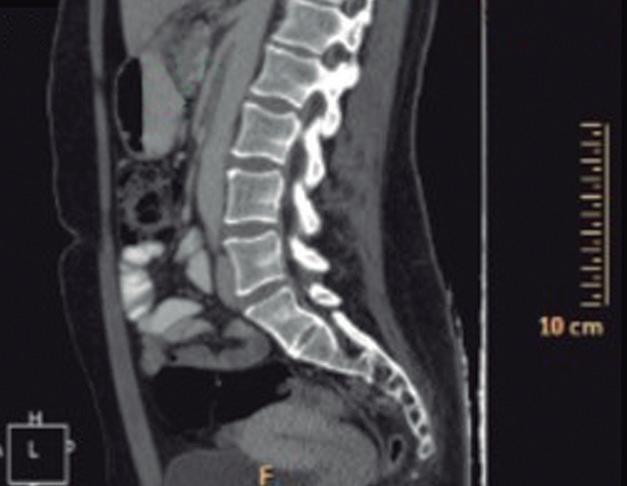

Se recuperaron 4781 VCC/pacientes: 13,1% en < 40 años, 5,8% en 40-44, 8,1% en 45-49 y 71,7% en ≥ 50; 62,1% femenino. El principal motivo de VCC fue diagnóstico en el 62,2%. El 80,4% con buena o excelente preparación (Tabla 1).

Pólipos colorrectales en menores vs mayores de 50 años Medardo Fernández-Chávez y col.

Se identificó al menos un pólipo en el 15,6% de los pacientes < 40 años, 19,4% en el rango 40-44, 21,6% en el de 45-49 y 34,6% en los ≥ 50 ( p < 0,001) (Figura 1).

Tabla 1. Características de las VCC analizadas, según los grupos etarios propuestos